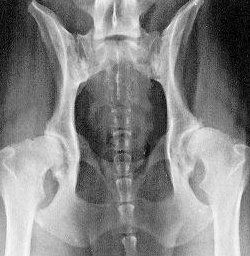

Vergelijk deze foto's eens en u kunt zeer waarschijnlijk zelf ook het verschil zien:

Op foto 2 ziet u duidelijk aangetaste heupen en de aansluiting is zeer onregelmatig. Deze heupen zijn duidelijk niet goed.